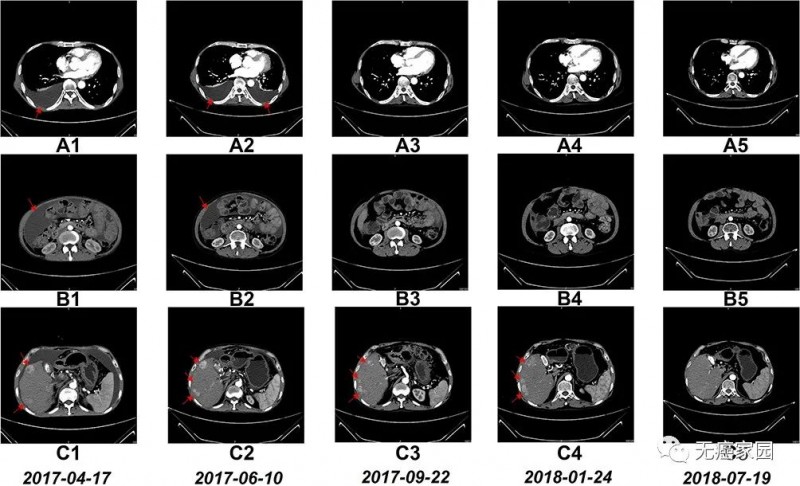

NK细胞治疗前和治疗期间的CT扫描结果

图A1~A5:CT扫描显示,6个疗程后胸腔积液完全消失;

图B1~B5:CT扫描显示,6个疗程后腹水几乎完全消失;

图C1~C5:CT:扫描显示,肝右叶多个肿瘤的大小在17 个疗程后显著缩小;

从2017年3月~2018年7月,他完成了17个疗程的NK细胞治疗,每个疗程每月进行一次,连续两天输注。值得一提的是,患者在NK细胞治疗期间未接受其他治疗。

6个疗程后,患者的胸水和腹水明显减少。自治疗结束以来,患者一直保持这种状态。此外,在NK细胞治疗17个疗程后,右肝叶中的多个肿瘤体积减小。